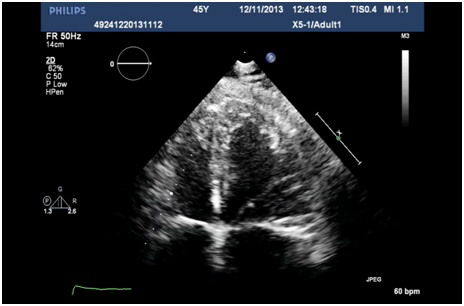

A 41 year-old-woman was admitted to our hospital for symptomatic complete atrioventricular block and atrial fibrillation. The patient had previously been diagnosed during childhood with partial atrioventricular septal defect and pulmonary valve stenosis; she had undergone at age 19 patch closure of primum ASD, repair of the left atrioventricular valve and open pulmonary valvotomy. She had a history of embolism in her right popliteal artery 10 years before admission for which she has been treated with oral anticoagulation. At admission, blood analyses including electrolytes were normal. Transthoracic echocardiography revealed a normal-sized left ventricle with good systolic function, increased left ventricular wall thickness and typical prominent trabeculations and intertrabecular recesses in the mid and apical segments of lateral and inferior wall pathognomonic for non-compacted myocardium (Figure 1A). Color Doppler imaging of the loosened myocardium demonstrated blood flow throughout the trabeculations (Figure 1B). Right ventricle was also mildly trabeculated with normal dimensions and preserved systolic function. There was no residual atrial shunt and there was mild left atrioventricular valve regurgitation and mild pulmonary valve stenosis. Cardiac MRI confirmed the diagnosis of left ventricular non-compaction with preserved left ventricular function, but also demonstrated the significant involvement of right ventricular myocardium (Figure 2).

Figure 1A Four-chamber echocardiographic view showing increased wall thickness in the left ventricular apical segments.